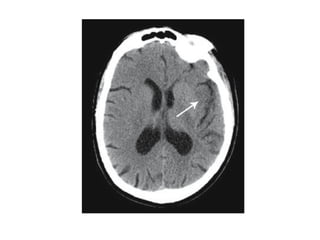

CT SIGNS

1.Hypoattenuating brain tissue

• The diagnosis is infarction, because of the

location (vascular territory of the middle

cerebral artery (MCA) and because of the

involvement of gray and white matter,

which is also very typical for infarction.